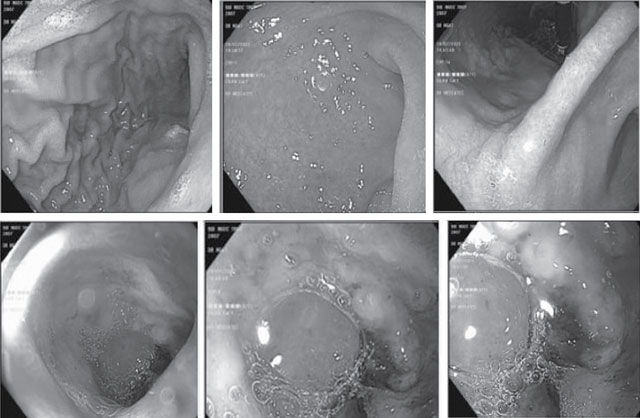

Đáng chú ý, kết quả nội soi thực quản, dạ dày, tá tràng cho thấy tổn thương viêm lỗ chỗ, có ổ loét sâu, kích thước 3-4 cm, có vết bầm đen. Bác sĩ chẩn đoán bệnh nhân xuất huyết tiêu hóa do loét hành tá tràng nên được nhập viện điều trị nội trú.